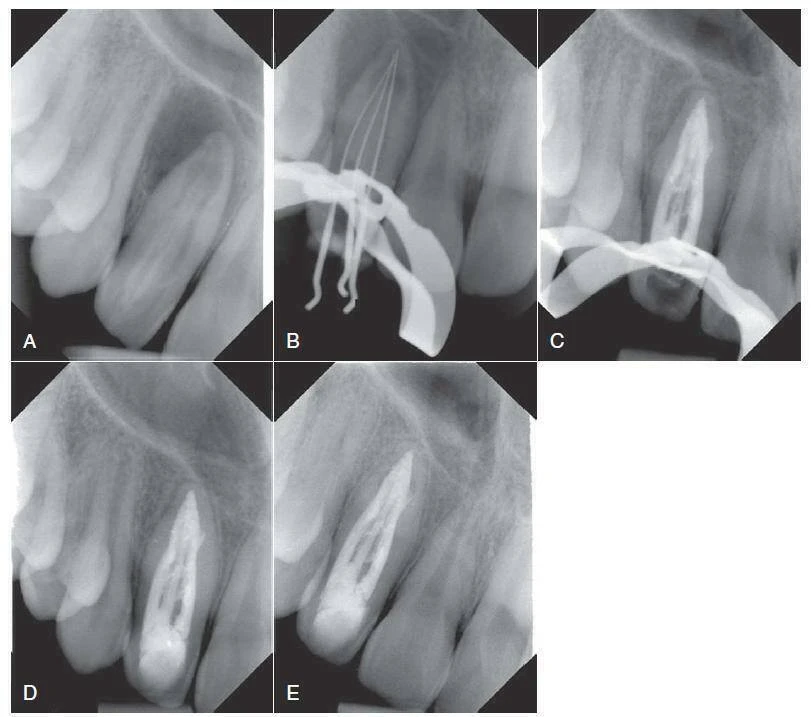

Nếu các triệu chứng lâm sàng kéo dài hoặc bắt đầu sau khi điều trị chỉnh nha, phẫu thuật có thể diễn ra bên cạnh điều trị ống tuỷ theo hướng thuận.Trong trường hợp ở hình 9-5, một tổn thương lan rộng tới xoang hàm trên và hốc mũi đã được điều trị bằng phẫu thuật 1 tuần sau khi điều trị ống tuỷ bình thường răng #7 và #8, cùng với việc lấy bỏ hai dụng cụ gãy. Tổn thương được nạo sạch hoàn toàn trong khi phẫu thuật, và mẫu mô được gửi đi sinh thiết để khẳng định mô bệnh học, tổn thương được chẩn đoán là nang chân răng. Đúng như dự đoán, bệnh nhân cảm thấy khá khó chịu sau phẫu thuật. Điều này cho thấy, tốt nhất nên tiếp cận bằng nội nha thông thường không phẫu thuật nếu có thể.

Hình 9.5 Khả năng và hạn chế của điều trị nội nha hướng thuận. Trong ca này, tổn thương rộng hàm trên bên phải được nạo bỏ và chẩn đoán mô học là nang chân răng. A – Hình ảnh phim cánh cắn trước điều trị cho thấy tổn thương rộng cận chóp ở hàm trên bên phải, cũng như hai dụng cụ phân biệt trên răng #7(Mũi tên). B – Hình ảnh phim chụp cận chóp sau điều trị của răng #7 và răng tuỷ hoại tử#8, được trám bít sau khi sử dụng thuốc canxi hyđroxit 2 tuần. Trám bít bằng lèn ngang với gutta percha và sealer 801 của Roth. C – Hai mảnh lentulo được lấy bỏ khỏi răng #7 (thước đo 0.5mm). D – Lát cắt mô học cho thấy biểu mô hô hấp và biểu mô vảy cũng như tế bào viêm, khẳng định chẩn đoán (C Courtesy Dr. I. Hegyi)